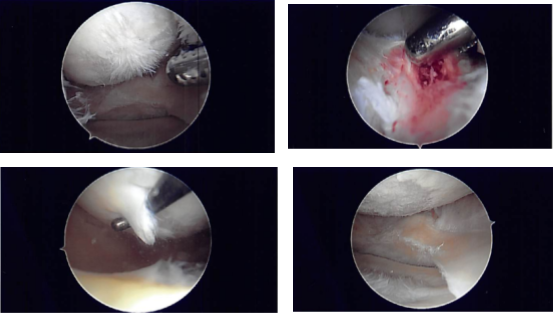

The patellofemoral compartment showed osteoarthritic changes. The medial compartment shows osteoarthritic changes as well as complex medial meniscus tear of the posterior horn and the body. The tear was resected using a straight biter or biter and shaver to stable margins.

A thin layer of the posterior meniscal tissue was left in the posterior body. The left femoral condyle chondroplasty was performed using a shaver. Now, the scope was moved to the intercondylar area, where ACL was seen. It was intact but frayed. ACL debridement was performed.

Intraoperative Arthroscopy Images

The scope was moved to the lateral femoral compartment, tibial femoral compartment where there was fraying of the med ial margins of the lateral meniscus as well as tear of the undersurface of the posterior horn of the lateral meniscus. The meniscus was debrided using a shaver.

There were osteoarthritic changes in the lateral femoral condyle, which was shaved. The scope was moved to the patellofemoral compartment, where arthritis was found in the undersurface of the patella as well as the trochlea. It was shaved using a shaver.

The new scope was now introduced into the medial compartment and the findings were rechecked and final shaving was performed. The knee was irrigated.